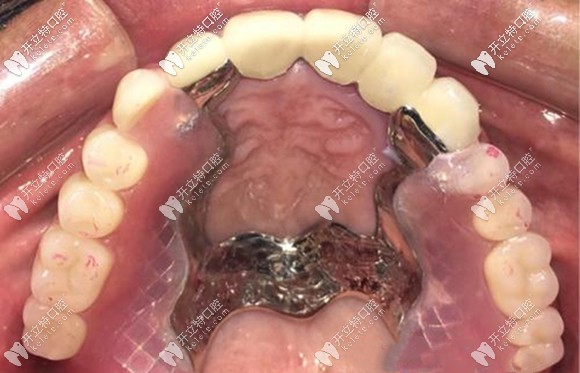

牙齒缺失或缺損后,許多人選擇做精密附著體義齒來修復(fù),而附著體假牙的種類繁多,如:如桿卡、球帽、磁性附著體、套筒冠、mk1、栓道等精密附件,作用和適應(yīng)癥也各有差異。